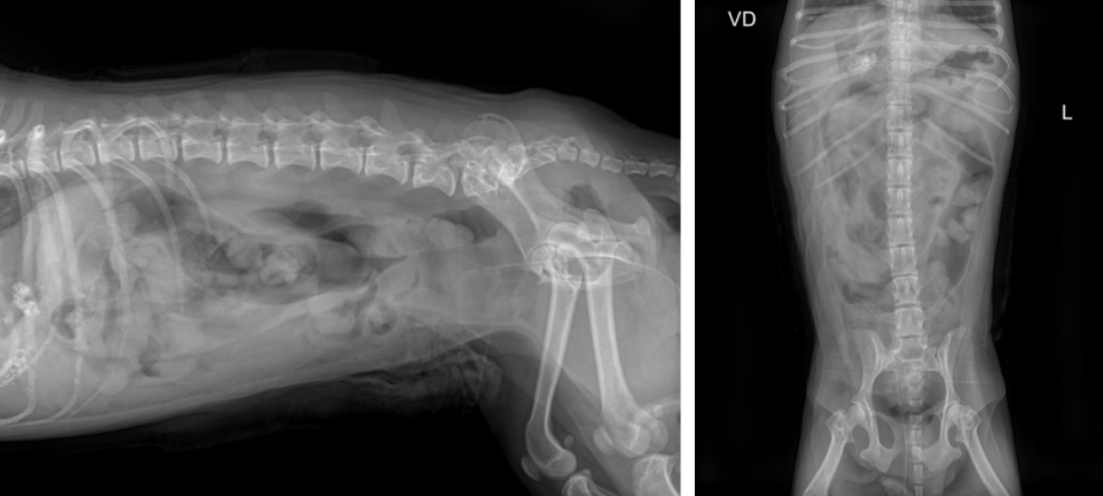

X-ray

방광(bladder) 부위에 다수의 방광결석(cystolith)이 의심되는 음영이 확인되었습니다.

Abdominal ultrasound(복부 초음파)

bladder wall(방광벽)이 두꺼워져 있어 chronic cystitis(만성 방광염)을 의심할 수 있는 소견

bladder 안에 다수의 결석(cystolith)이 확인되었고, urethra(요도) 방향으로도 여러 개의 결석이 내려가 있는 상태가 확인되었습니다.